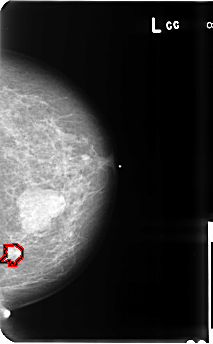

B_3512_1.LEFT_CC

FILE: B_3512_1.LEFT_CC.OVERLAY

TOTAL_ABNORMALITIES 1

ABNORMALITY 1

LESION_TYPE CALCIFICATION TYPE PLEOMORPHIC DISTRIBUTION CLUSTERED

LESION_TYPE MASS SHAPE IRREGULAR-ARCHITECTURAL_DISTORTION MARGINS SPICULATED

ASSESSMENT 5

SUBTLETY 4

PATHOLOGY MALIGNANT

TOTAL_OUTLINES 1

BOUNDARY